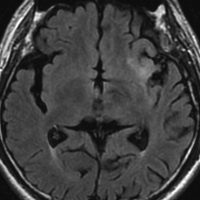

2010年無症状の時の画像です。こんなのを手術で摘出したら認知機能が落ちて人格が変わります。だから経過観察しました。

2015年のテモゾロマイドを開始する前の画像です。2014年にちょびっと生検術をして1p/19q欠失,IDH変異はわかっていました。2015年に全般発作を起こしたので治療を開始しました。テモゾロマイドを 2年 24コース続けました。乏突起膠腫は大きくなる時,てんかんを生じることが多いです。

2020年の画像です。腫瘍はかなり小さくなって再燃(再発)していません。てんかんも抑制されて発作はありません。無症状です。

この例は,手術も放射線治療もしないで,乏突起膠腫が10年以上,制御できることを示しています。また,テモゾロマイド治療でてんかん発作が少なくなることも有名な事実です。

でも,現実はこんなに甘くない?  2025年時点で,治癒を目指すなら低線量放射線治療を加えるべきと考えられています。